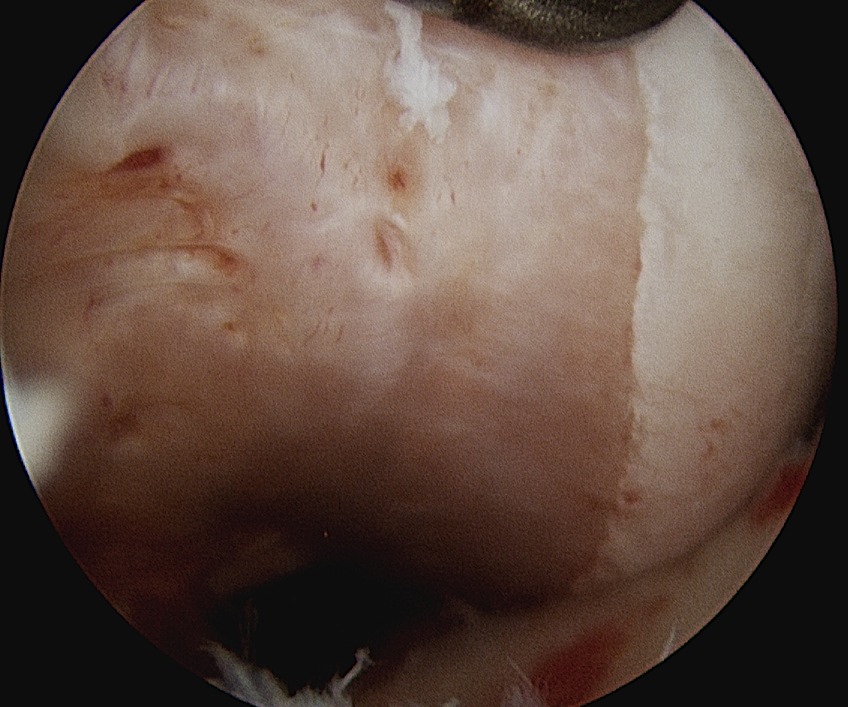

Cruciate ligament ganglion

Technique

Surgical technique PDF using trans-septal portal

- 85 intra-articular ganglions

- 49 ACL, 16 PCL

- 12 from anterior horn meniscus, 3 posterior horn meniscus

- 3 from fat pad

Technique

Surgical technique PDF using trans-septal portal